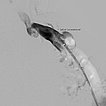

Die Phlebographie nach Direktpunktion des venösen Malformationsanteils zeigt eine großlumige Drainagevene, die in der Kniekehle mit der V. poplitea kommuniziert. Diese muss zunächst verschlossen werden, da sonst das Sklerosierungsmittel darüber abfließen könnte und potentiell eine Thrombose der tiefen Leitvenen des Beins (und eine Lungenembolie) verursachen könnte. Zudem besteht grundsätzlich ein erhöhtes Thrombembolierisiko bei der Patientin, dass durch den Verschluss deutlich vermindert werden kann.

Dazu wird zunächst über einen Einführungsdraht eine großlumige Einführungsschleuse vorgebracht, die zum Einführen der Laserfaser dient. Dieser wird über die Vene bis zum Kommunikationspunkt in der Kniekehle vorgeschoben.

Durch diese Schleuse wird eine Laserfaser zur endovaskulären Lasertherapie vorgeführt. Durch die Erhitzung des Laserstrahls kommt es zu einer massiven Reizung der Venenwand, die sich anschließend sehr schnell verschließt. Um die Laserspitze kommt es sofort zur Thrombusbildung (weiß, da als Kontrastmittelaussparung sichtbar).

Nach Verschluss durch die Laserfaser und Anspritzen über die zurückgezogene Schleuse kommt es nicht mehr zu einem Abstrom des Kontrastmittels über die Kommunikationsvene, die erfolgreich verschlossen ist. Es kontrastiert sich nur noch die venöse Malformation. Diese ist jetzt bereit zur Sklerosierungsbehandlung, da dieses nicht mehr abfließen kann.